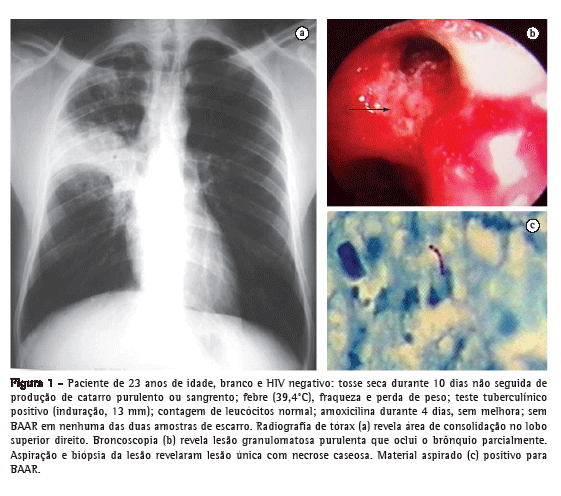

Observou-se consolidação pulmonar nos lobos superiores, principalmente no direito, em 40 (67,8%) dos casos, uma frequência significativamente maior que a observada em outros locais (p < 0,001), embora o lobo médio tenha sido afetado em 9 casos (15,3%). Pequenos focos isolados, adjacentes à lesão principal, foram observados na maioria dos pacientes (Figura 1).

Obteve-se confirmação microbiológica principalmente por meio de baciloscopia, que foi positiva para BAAR em 41 (69,5%) dos 59 pacientes. Realizou-se broncoscopia em 18 pacientes (30,5%). Lesão da parede brônquica foi identificada e submetida a biópsia em 8 (44,4%) dos 18 pacientes. Os achados claramente indicaram a presença de fístula em 3 (16,7%), ao passo que em 5 (27,8%), os achados sugeriram a presença de fístula (evidência de cicatrização). Nos 8 pacientes, as alterações foram identificadas em grandes brônquios. Nos 18 pacientes submetidos a broncoscopia, fez-se o diagnóstico microbiológico por meio da análise das amostras da biópsia ou do LBA (Tabela 4).

Em nosso estudo, a presença de tosse seca antes dos demais sintomas respiratórios e dos sintomas sistêmicos sugeriu o diagnóstico clínico de pneumonia tuberculosa. A presença de bloco de consolidação e pequenos focos isolados adjacentes na radiografia também eram indicativos da condição. Embora a confirmação microbiológica geralmente se dê por meio de baciloscopia, é ocasionalmente necessário coletar amostras por meio de broncoscopia, como ocorreu no presente estudo. Já que esse tipo de lesão frequentemente contém poucos germes, podem ser necessários múltiplos exames de escarro para detectar BAAR.